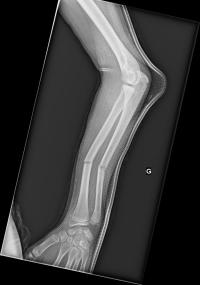

Fracture de l’avant-bras 31 mars 202519 mars 2024 par Damien Traitement Traitement orthopédique Embrochage centro-médullaire